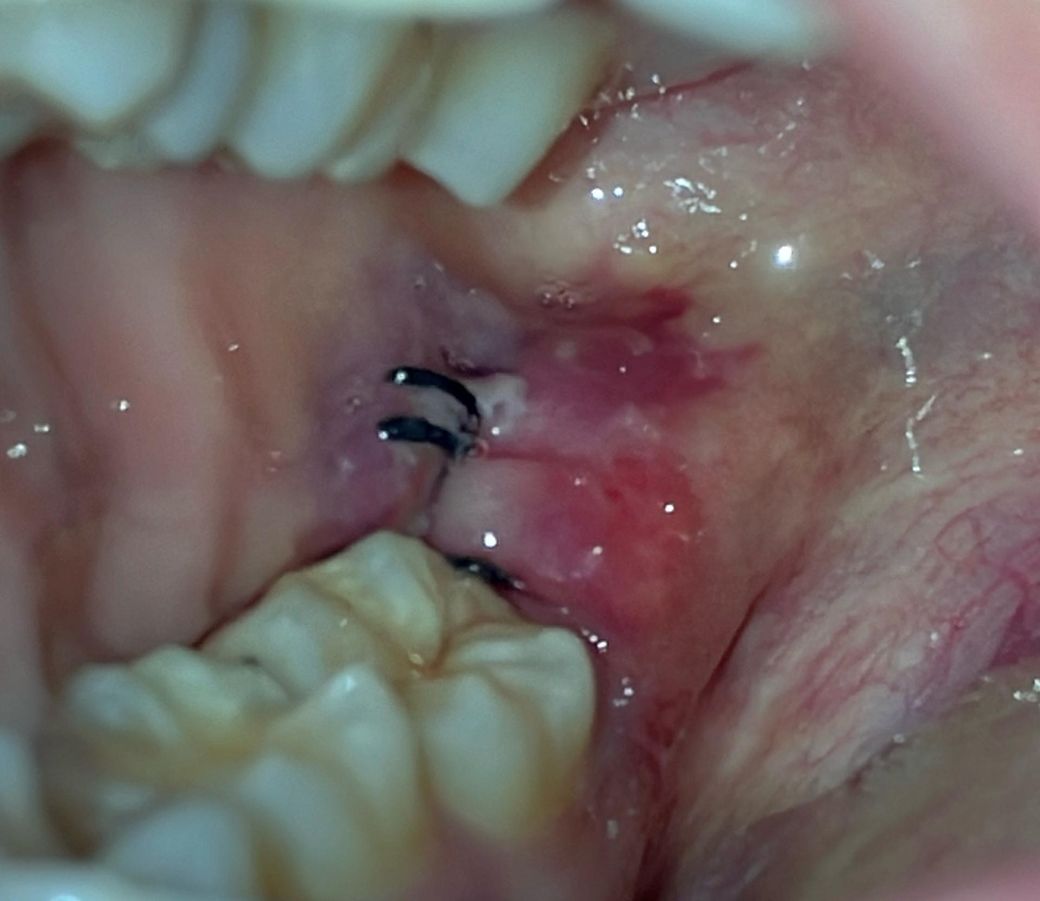

하악 수평매복사랑니 발치한 지 73시간 정도 됐습니다

통증 아예 없고 얼굴 붓기도 99% 가라앉았는데 잇몸 봉합 부위는 꽤 부어있습니다

근데 다른 분들 후기 사진과는 달리 봉합 부위가 너무 붉고 많이 얼룩덜룩한 것 같아서ㅠㅠ

혹시 뭐가 잘못된 걸까요?

발치 부위 염증이 다소 있습니다만 입이 안벌어지거나 전신발열이 있는게 아니라면 큰 문제는 아닐 것 같습니다 해당부위 양치질 살살 해서 위생관리해주세요